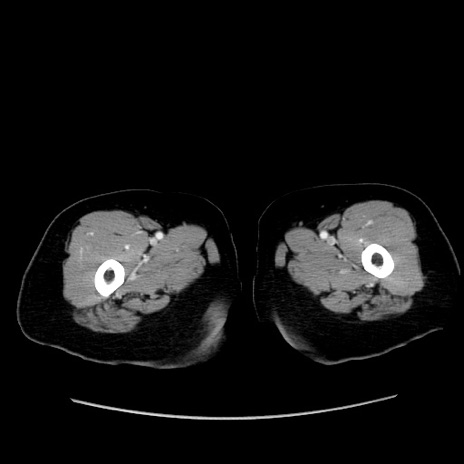

冠状断像